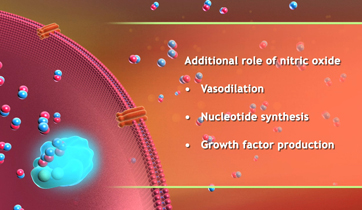

Natracor; hBNP MOA

Scios Pharmaceuticals

Adair Greene Advertising

Natracor treats congestive heart failure triggered by the renin - angiotensin - aldosterone system which causes sodium and fluid retention and vaso-constriction. hBNP is a regulatory hormone, which binds to Guanylate cyclase receptors to reverse effects.